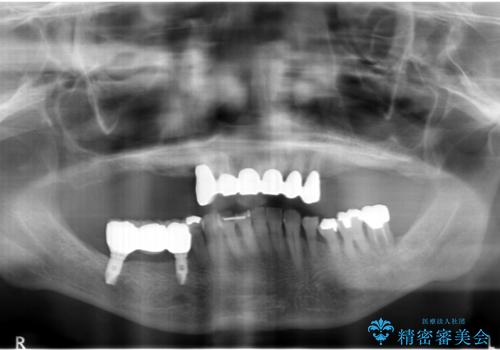

- 上の奥歯がないまま長年過ごしていたら前歯もぐらぐらしてきてしまったことを主訴に来院された患者様です。

奥歯の咬み合わせがないことにより前歯に負担がかかり動揺が出ていました。

精査したところ右下の奥歯も歯周病により保存不可能な状態でした。

なるべく予算を抑えたいとのご希望から、上顎は入れ歯、右下臼歯部はインプラントによる治療を行いました。

上の前歯は動揺を抑え、入れ歯の着脱にも耐えうるように被せ物を連結させることにしました。